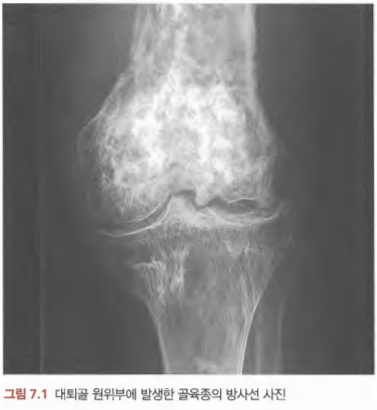

- Osteosarcoma: 20-30대, 주로 하지 관절, x-ray상 bone destruction(moth-eaten), osteomyelitis 감별 요함.